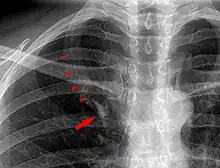

Azygos lobe

In human anatomy, an azygos lobe is a normal anatomical variation of the upper lobe of the right lung.[1] It is seen in 0.3% of the population.[2] Embryologically, it arises from an anomalous lateral course of the azygos vein,[3] in a pleural septum within the apical segment of the right upper lobe or in other words an azygos lobe is formed when the right posterior cardinal vein, one of the precursors of the azygos vein, fails to migrate over the apex of the lung and penetrates it instead, carrying along two pleural layers as the azygous fissure, that invaginates into the upper portion of the right upper lobe.[1]

An azygos lobe is usually an incidental finding on chest x-ray or CT scan. It is asymptomatic and not associated with any morbidity.[4][5] However, it can cause technical problems in thoracoscopic procedures.[6] The presence of the azygos lobe could alter the normal location of the superior vena cava or may be associated with other anomalies, including esophageal atresia or intrapulmonary right brachiocephalic veins.[7]